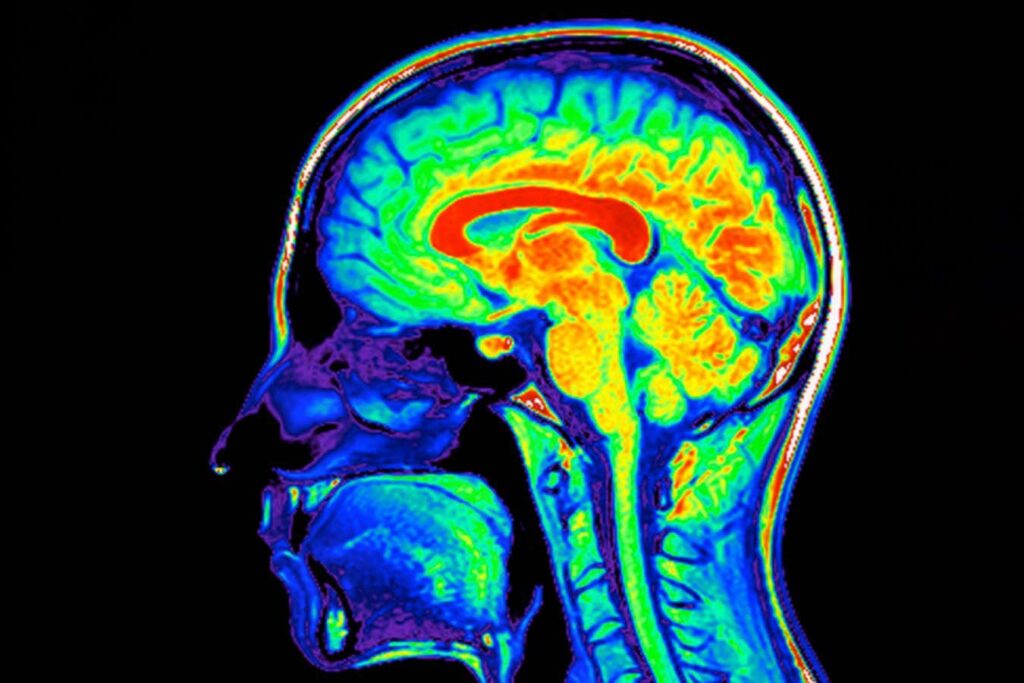

Magnetic resonance image scan of the human brain

Phanie/Sipa Press/Alamy